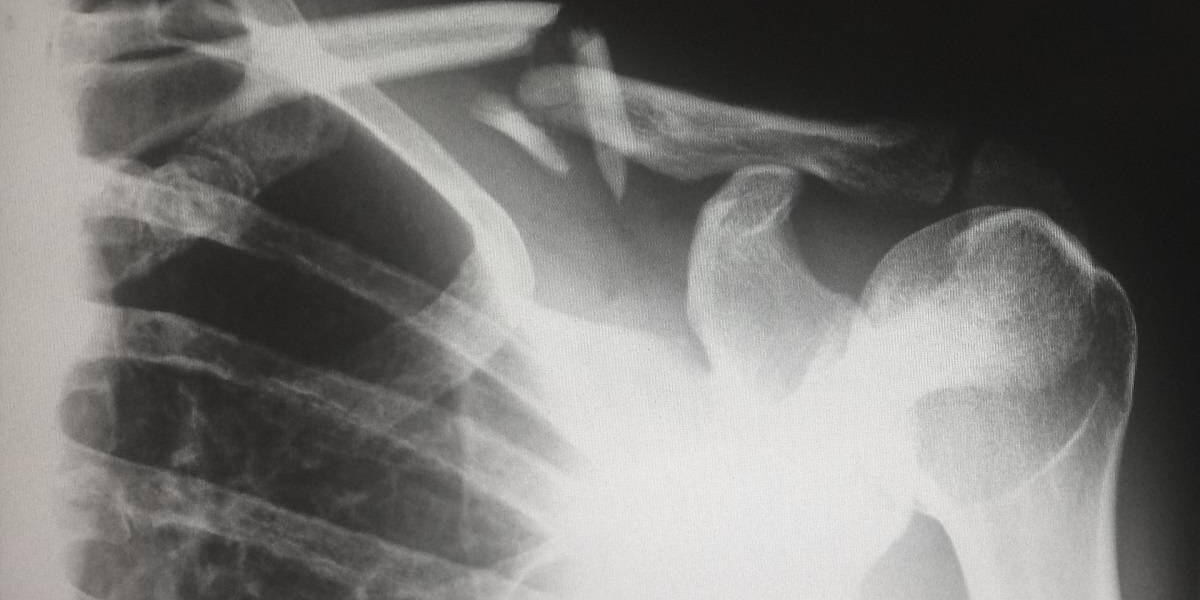

Patiënten met een eenvoudige botbreuk en stabiel letsel hoeven niet langer voor een controlebezoek naar het ziekenhuis te komen. Het Medisch Centrum Leeuwarden (MCL) implementeert daarvoor de Virtual Fracture Care (VFC)-methode. Normaliter kregen bijna alle patiënten met een verstuiking of botbreuk een afspraak voor een controlebezoek in het ziekenhuis, maar onderzoek toont aan dat dit vaak niet nodig is.